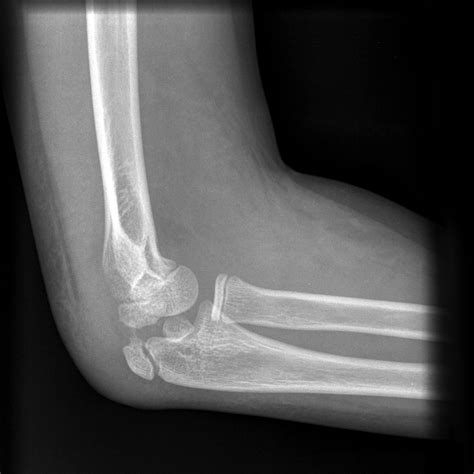

• X-Rays: X-rays are the primary imaging tool used to diagnose hairline fractures. They can show the crack in the bone and help determine the extent of the injury.

• CT Scans: In some cases, a CT scan may be ordered to provide a more detailed view of the bone and surrounding tissues.

• MRI Scans: An MRI may be used to assess soft tissue damage and confirm the diagnosis of a hairline fracture.